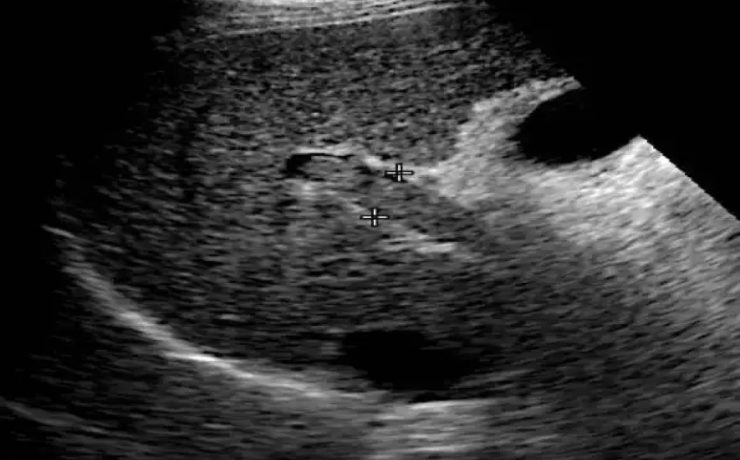

Patologías benignas de la próstata: prostatitis e hiperplasia benigna

En este estudio se llevó a cabo un análisis de la anatomía prostática; los factores más relevantes que regulan el crecimiento prostático y y las funciones de la glándula que podrían influir en la etiología de diferentes patologías de la próstata; parámetros claves en el diagnóstico temprano y de estas